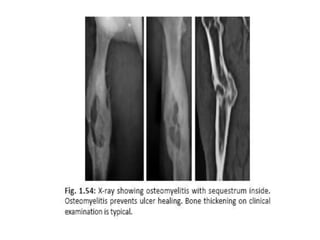

• X-ray of the part to look for

periostitis/osteomyelitis.